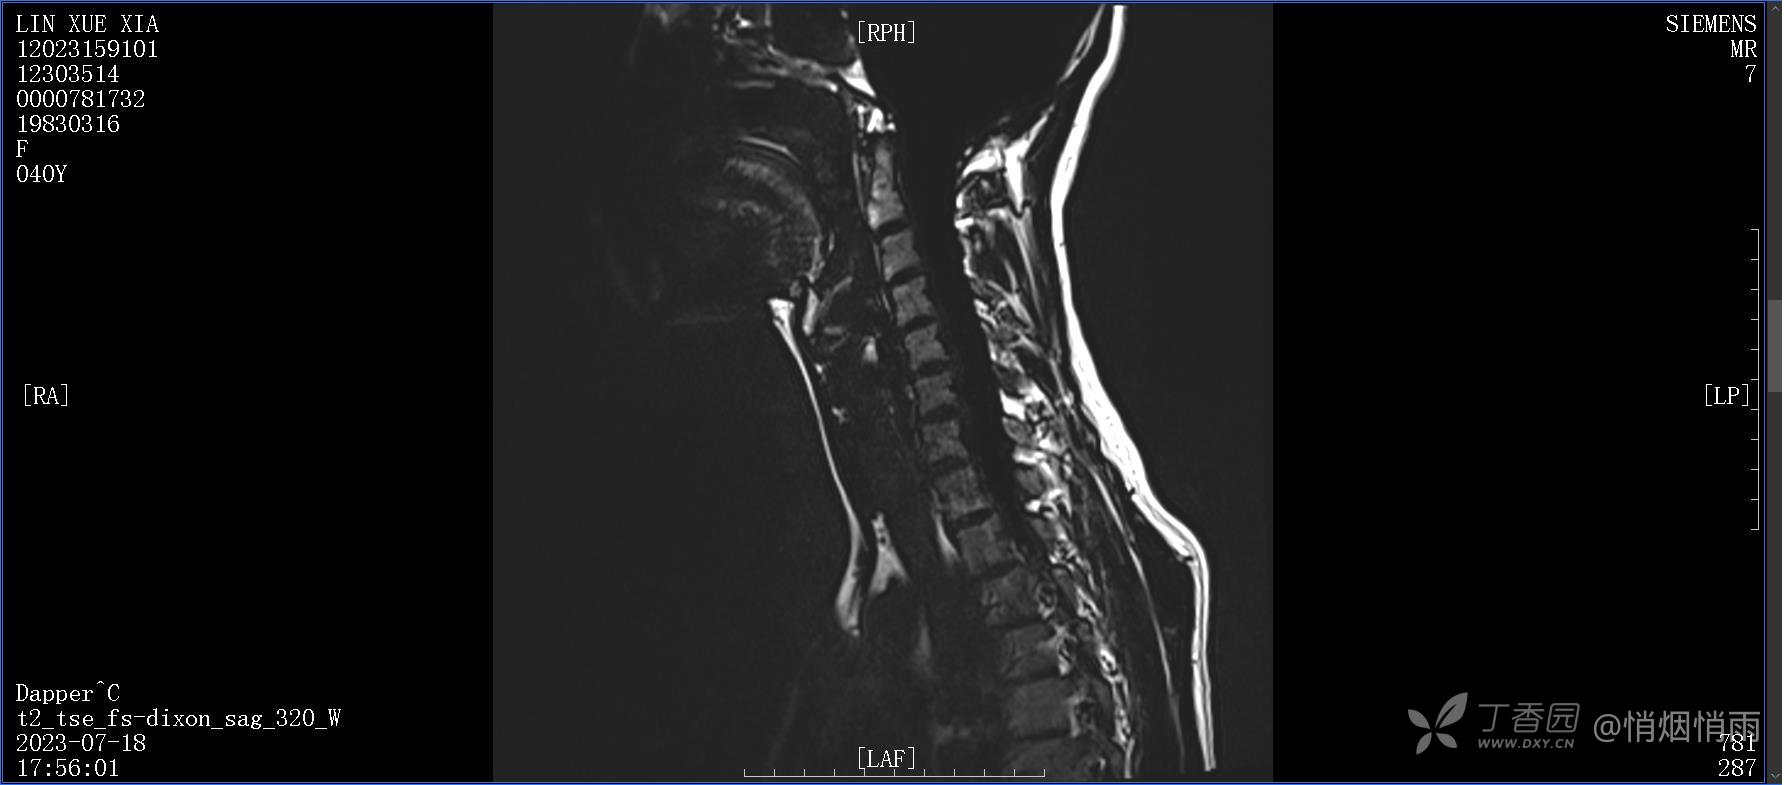

NeurothinkerZ 推荐患者女性,40岁,因右肩背部疼痛班活动受限4日余入院(2023-07-17)。

病史:入院前4天无明显诱因突然感右肩背疼痛伴随活动受限,自行口服依托考昔、艾瑞昔布等药物治疗,院外应用肩关节局部手法按摩等,均无明显改善。外院门诊诊为颈椎病。自诉既往多次“胸椎小关节紊乱”于当地诊所行手法按摩,治疗后好转,否认慢性疾病病史、外伤史、手术史,诉青霉素过敏,无其他药物食物过敏史,否认吸烟史、饮酒史,月经正常,经量正常。

查体:右肩关节局部轻度肿胀,肩胛区压痛明显,痛处不固定,肩关节痛性活动受限,jobe test(+),lift -off test(+),中指、环指感觉较余指减退,余肢端感觉及血运情况可。

目前的诊断,暂时依据辅助检查诊为肩袖损伤,但是患者疼痛的性质和特点,却不是单纯的肩袖损伤所致。考虑过胸廓出口综合征,但是该疾病会出现肩胛区的疼痛吗?(由于考虑到费用的问题,没再进行下一步的检查)带状疱疹会有如此的症状吗?